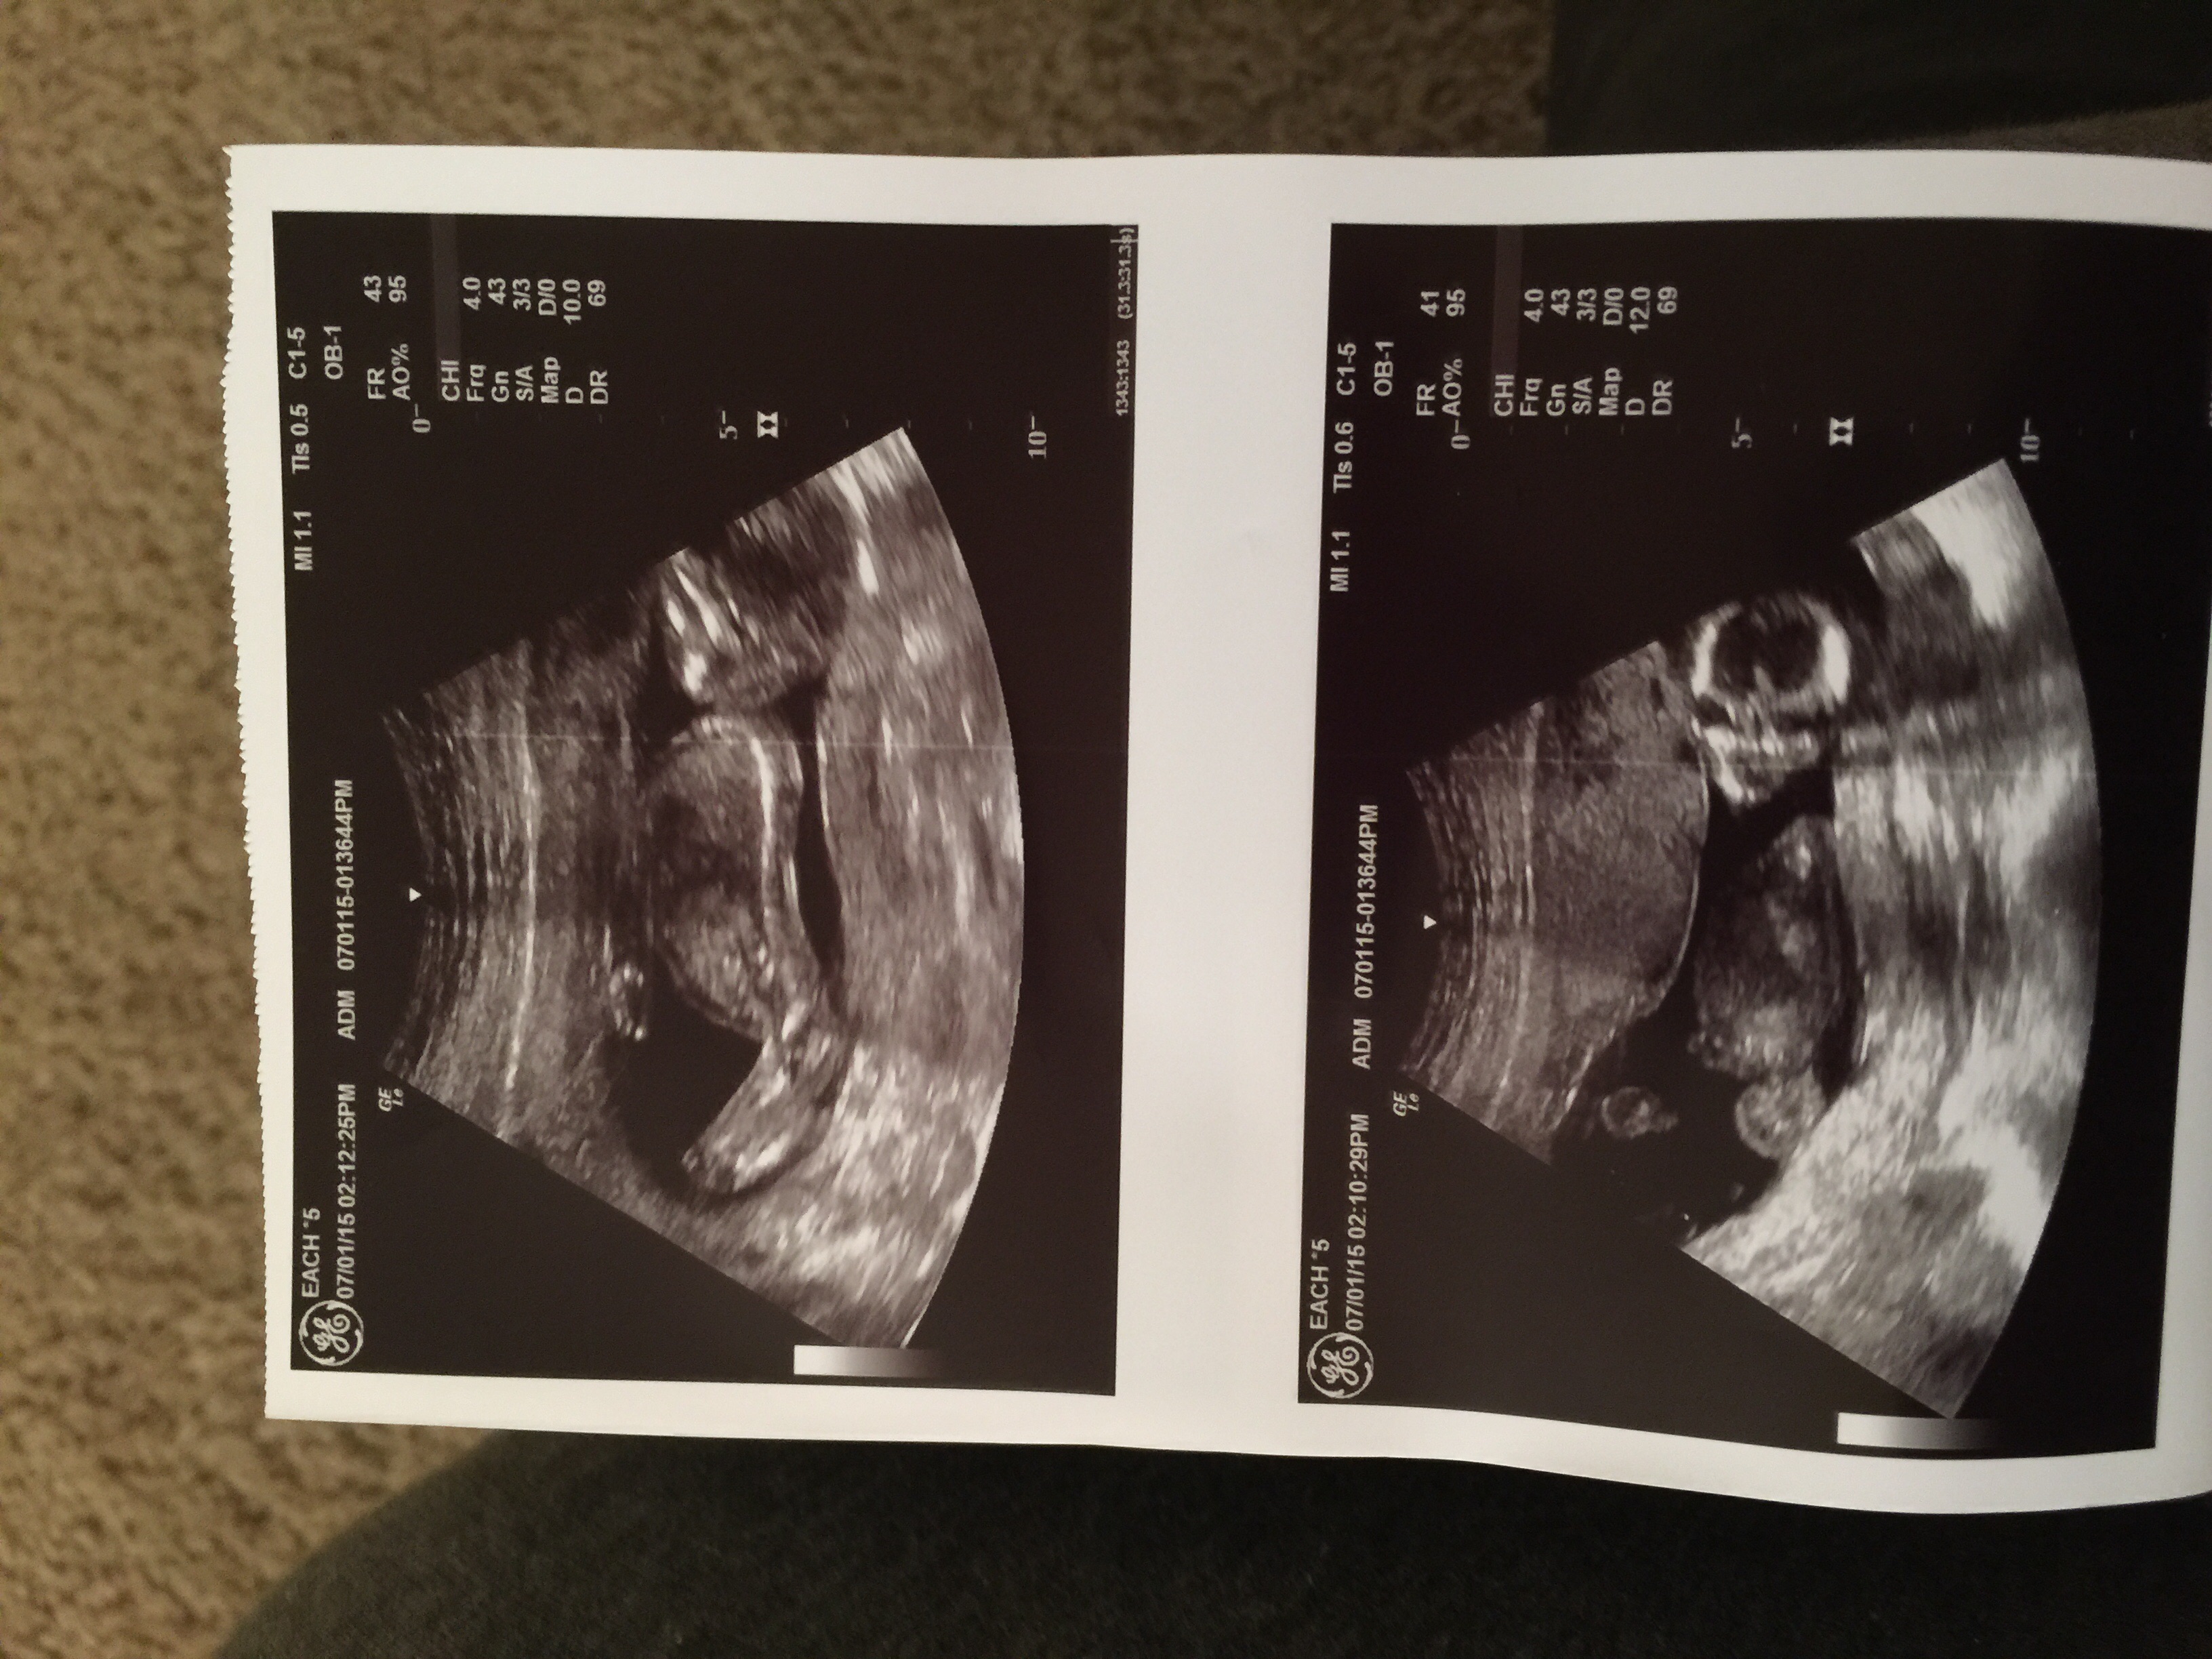

It's a boy at 16w2d

went for a normal check up and it's a boy we are so excited our daughter has been saying it's a boy from the start

image.jpg